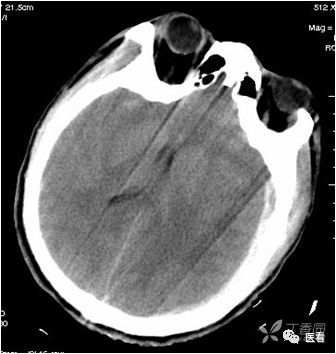

有躁动、呼吸运动和非自主运动(心跳、胃肠道蠕动)所致的伪影。

本例因为躁动明显,产生的伪影显著、杂乱。